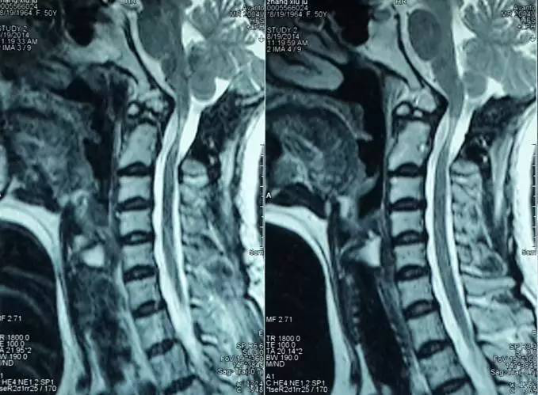

3影像学检查

手术前前屈位X光片寰枢椎脱位(寰齿前间隙7mm)。寰枢椎三维CT见寰枕融合,颅底陷入(齿状突位于钱氏线上14.2mm),右侧枢椎椎弓根发育狭小(小于2mm),磁共振显示小脑扁桃体下疝、颈髓损伤伴椎管狭窄。

4术前片子